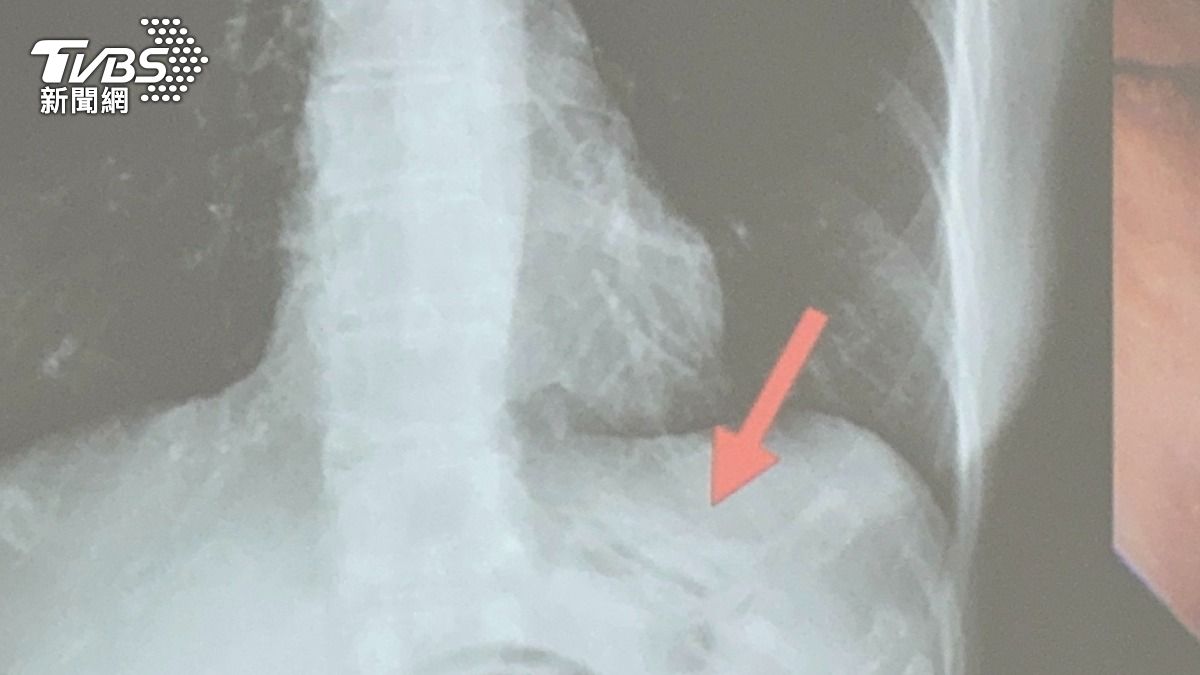

臺中醫院肝膽腸胃科醫師吳明駿指出,60歲女性患者因動脈瘤破裂接受腦部手術,術後恢復良好,但吞嚥功能受損無法以口正常進食,所以接受吞嚥訓練復健治療,未料在拔除鼻胃管的時候,患者感到上腹疼痛不適,且在移除鼻胃管的過程中,感覺有非常大的阻力;因擔心鼻胃管放置產生相關的併發症,醫療團隊立即幫病人照了一張X光,才發現鼻胃管在胃裡面打結了。

經醫師跟患者與家屬說明,患者接受無痛胃鏡檢查,吳明駿醫師利用異物夾將打結的鼻胃管解開拉直後,順利的移除鼻胃管。